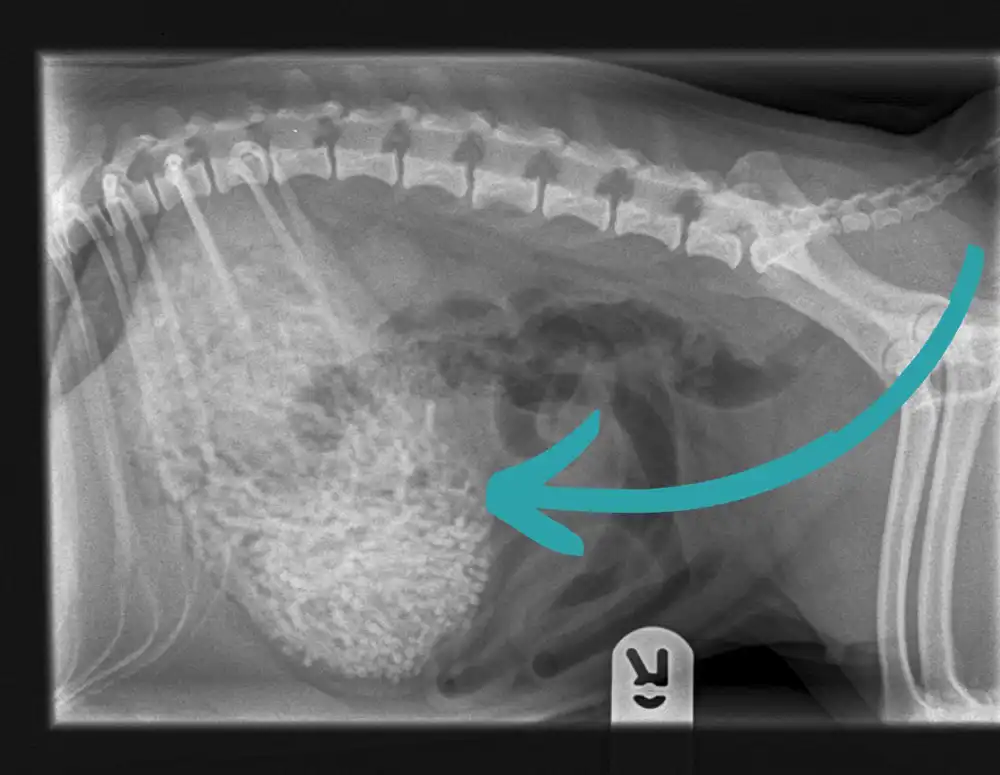

“Initial investigations by our team revealed that she had something rather ‘strange’ looking in her stomach and she was swiftly taken to surgery for further investigations,” a Newton Clarke spokesperson said.

“To our surprise, Ham had a stomach full of hairbands – over 200g of them to be exact.”

X-rays showed an unusual shape in Ham’s tummy. Picture: Newton Clarke